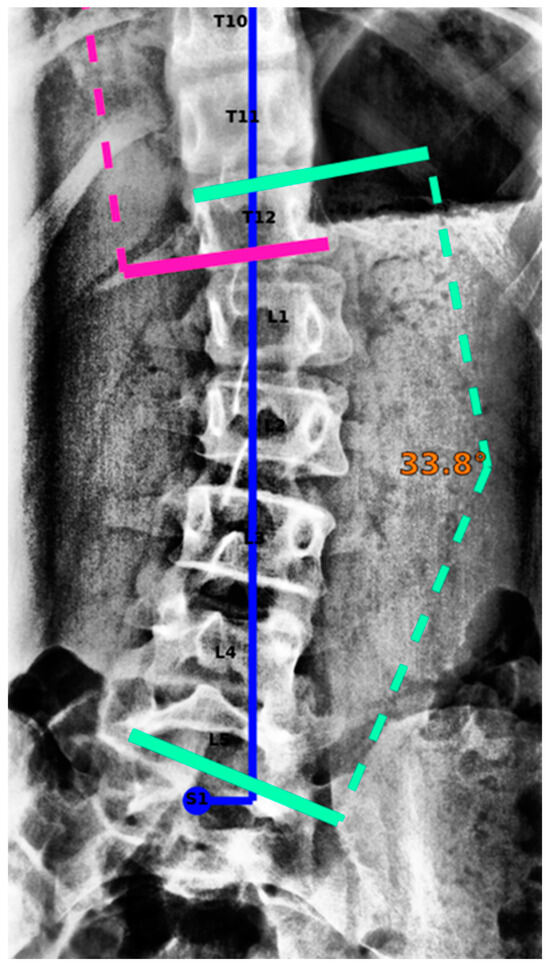

2.3. AI Model and Algorithms